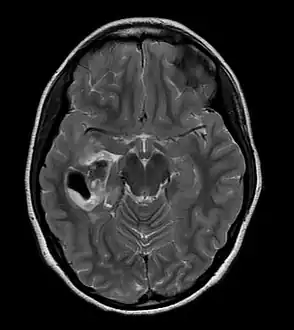

Pleomorphic xanthoastrocytoma (WHO grade II); Pleomorphic xanthoastrocytoma represents a distinctive glioma subtype

PXA as visualized on an MRI

- A CT scan of the brain, and/or an MRI scan of the brain and spine, will be performed. A special dye may be injected into a vein before these scans to provide contrast and make tumors easier to see.